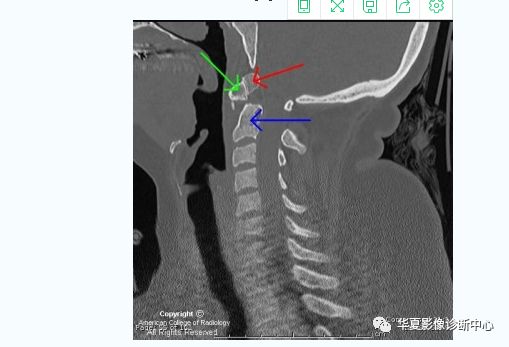

【影像图片】CT MPR图像

【影像表现】:The coronal CT neck image in Figure 1 shows a small, round os odontoideum (red arrow) separated from the body of C2 (blue arrow) by a wide radiolucent gap. It has smooth and uniform cortical margins.冠状位CT显示一个小圆形的齿突(红箭),与颈2椎体分离(蓝箭),皮质边缘均匀平滑。

The sagittal CT neck image in Figure 2 shows signs of C1 anterior arch hypertrophy (green arrow). There is no paravertebral swelling. The posterior atlanto-dens interval (PADI) also known as the space available for cord (SAC) is 12mm (less than 13mm has a poor prognosis).

矢状位的CT显示颈1椎体前弓肥大(绿箭),无明显椎旁肿胀。后方寰齿间距(又称脊髓可用空间)约12mm(小于13mm预后不良)